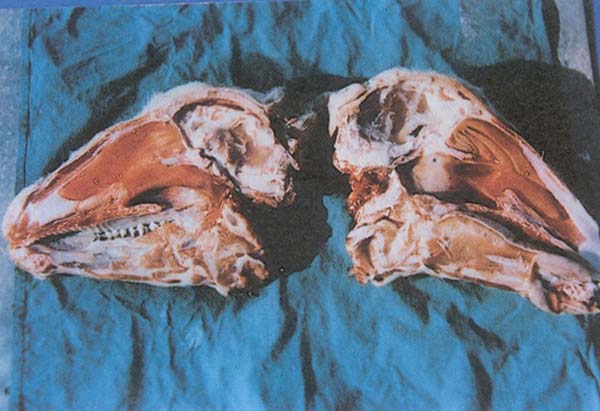

- Beyindeki ince duvarlı kist (Şekil 167)

Şekil 167 : Coenurus cerebralis. Beyindeki ince duvarlı kist.

Yargı : Koenurozdan etkilenen karkas onaylanır . Etkilenen beyin ve organlar kınanır .

Ayırıcı tanı : Abse, kanama, beyin tümörleri ve erken evrelerde beyin iltihabı ve kuduz